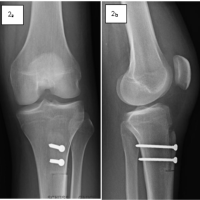

Fastly, a lateral tibial pre-modulated locking plate was applied to prevent further fracture propagation and avoid prolonged cast immobilization (Fig. 4). The same unlocked knee extension brace was recommended, along with a full weight-bearing protocol. Ten months after the plating procedure, the proximal tibial stress fracture had consolidated, with the KOOS score evaluated at 90.5 at that time (Fig. 5). Later, the patient underwent the removal of all hardware successfully (Fig. 6).

Figure 4: Anteroposterior view (a), lateral view (b) demonstrate the immediate post-surgical view of fracture fixation with lateral tibial pre-modulated locking plate.

Figure 5: Coronal view (a) and sagittal view (b) computed tomography images demonstrate good consolidation of the fracture site.

Figure 6: Anteroposterior view (a) and lateral view (b) demonstrate the post-removal tibia, showing a well-healed fracture site.